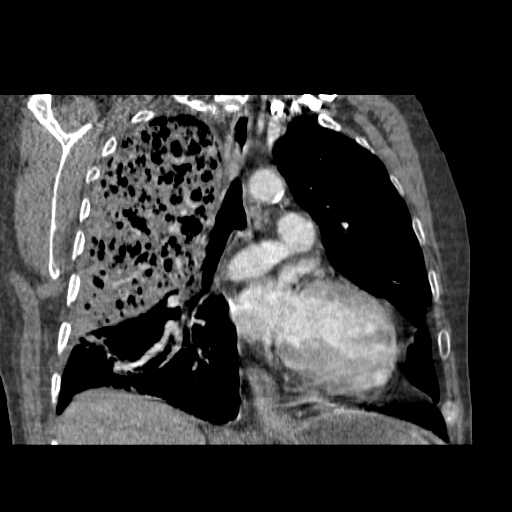

2008.8.17ct

病变从8.11-8.17明显改变,增多,以蜂窝状改变为主,类蜂窝肺,似弥漫性肺泡癌,但是病变进展太快,不符合弥漫性细支气管肺泡癌。因此考虑为特殊微生物感染,多以霉菌类常见,建议细菌微生物学检查。

疑点二:影象表现怪异,大片阴影内见多发筛孔征,如何解释.

间质为主,血管炎性水肿?